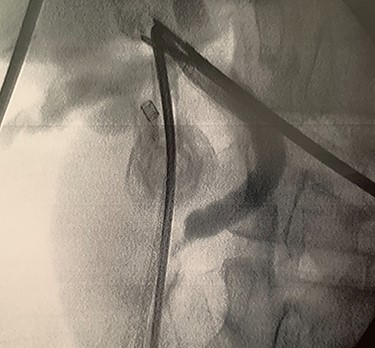

A trans-cystic cholangiography was then performed, using a 5.0 Fr COOK® Medical ureteral catheter inserted through epigastrium. The augmented caliber of CBD and the presence of prepapillary lithiasis were confirmed. No contrast could pass into the duodenum (Fig. 3).

Trans-cystic cholangiography demonstrating prepapillary lithiasis.